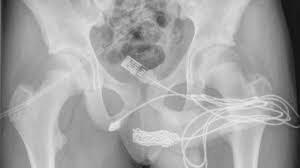

De acordo com o tabloide inglês Daily Star, o jovem, que não teve o nome revelado, foi levado ao hospital e passou por uma radiografia, que mostrou a gravidade da situação. O cabo não apenas ficou preso na parte interna do pênis, como também fez alguns nós e ficou emaranhado na uretra..

"O paciente era um adolescente saudável e em boa forma, sem histórico de distúrbios de saúde mental. As duas pontas do fio USB estavam saindo do meato uretral externo, enquanto a parte do meio do fio permanecia dentro da uretra", escreveram.